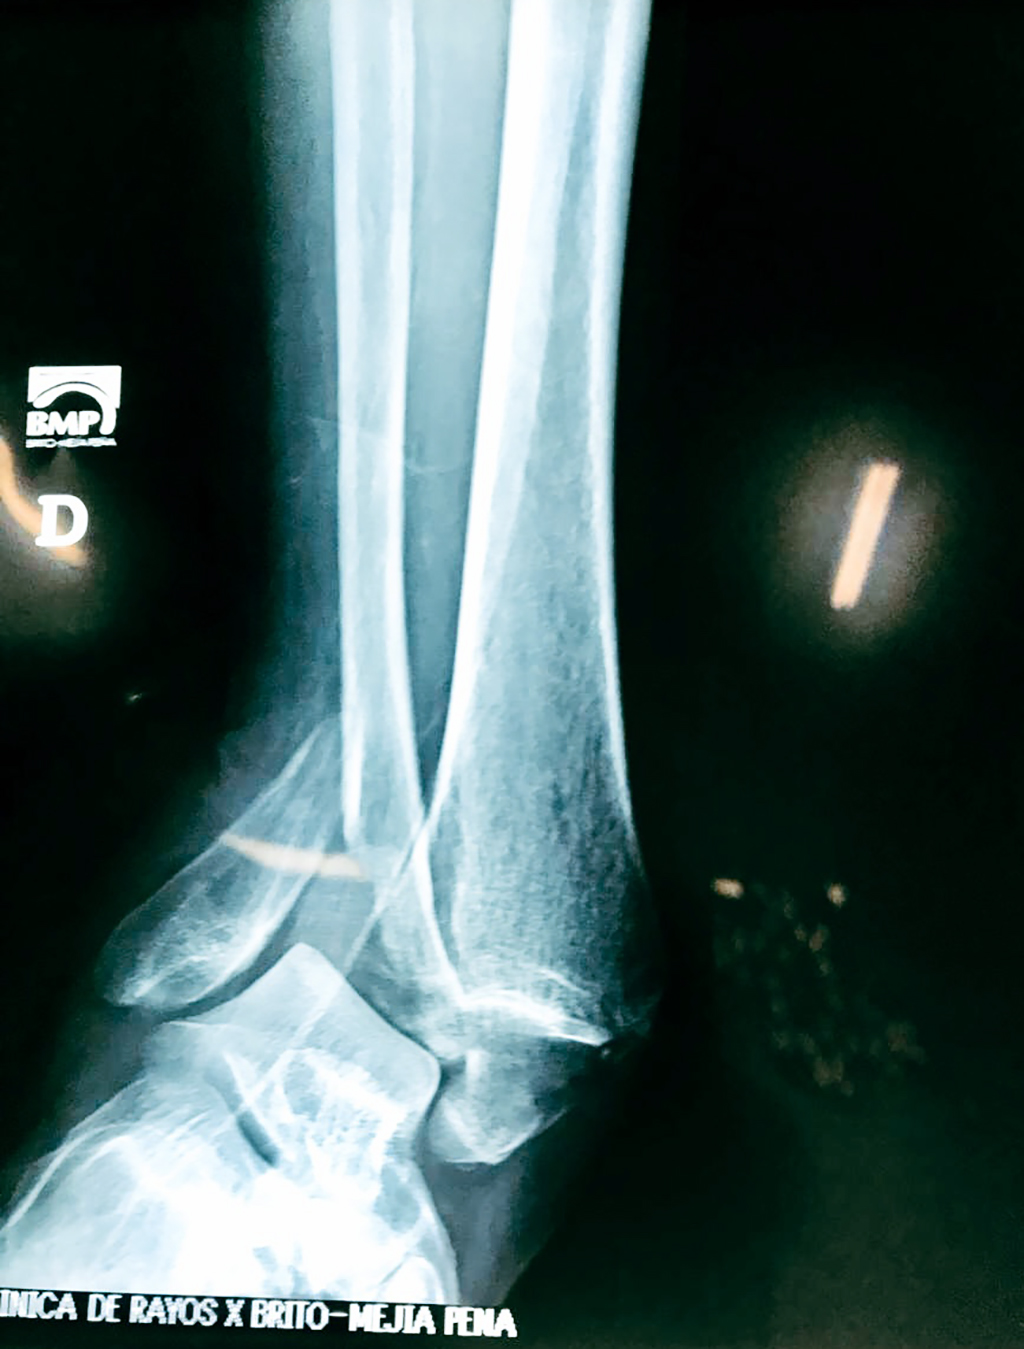

Cuando se necesita cirugía, es probable que esta implique el uso de clavijas de metal, tornillos o placas para sostener los huesos en su lugar mientras la fractura se consolida. Los elementos de soporte pueden ser temporales o permanentes.